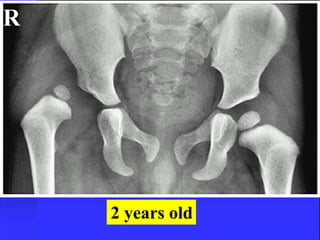

R

2 years old

= Femoral neckdisplaces ant. producing an apparent varus, the head is posterior = Occurs through Zone of hypertrophy